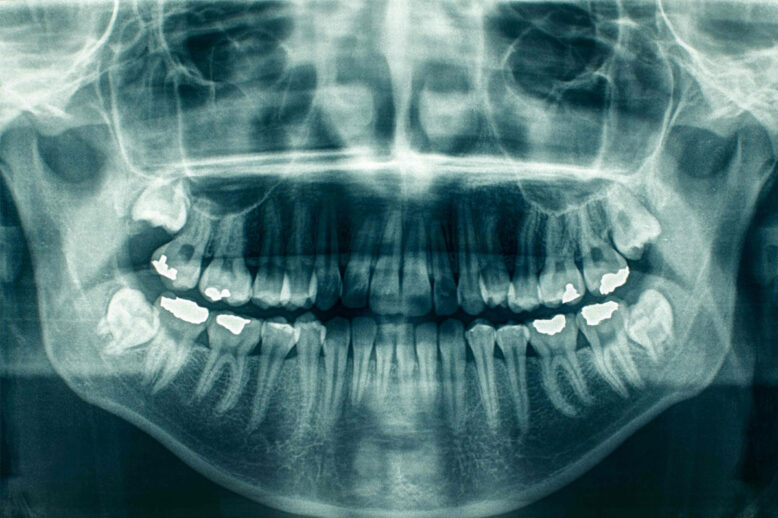

Panorex X-Ray

You might be familiar with dental X-rays wherein the dentist places a piece of plastic inside your mouth for you to bit down on and takes multiples images that show one or a couple of your teeth. This is just one type of X-ray. There are many others, one of them being a panoramic dental…